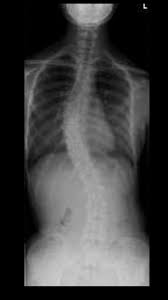

側 弯症側 手術側 ブログ側 ☆延長手術・・・☆側 -側 側わん症:VEPTRの会側 手術が必要な側弯症側 |側 ブログ側 |側 東京都品川の整体なら東京脊柱専門整体院側 側弯症対策!手術を避けるために日常で気をつけること側 |側 大阪市西淀川区佃の整体「なかむら鍼灸接骨院」千船駅徒歩4分側 側弯症コルセット側 術後側 手術が必要な側弯症5選側 -